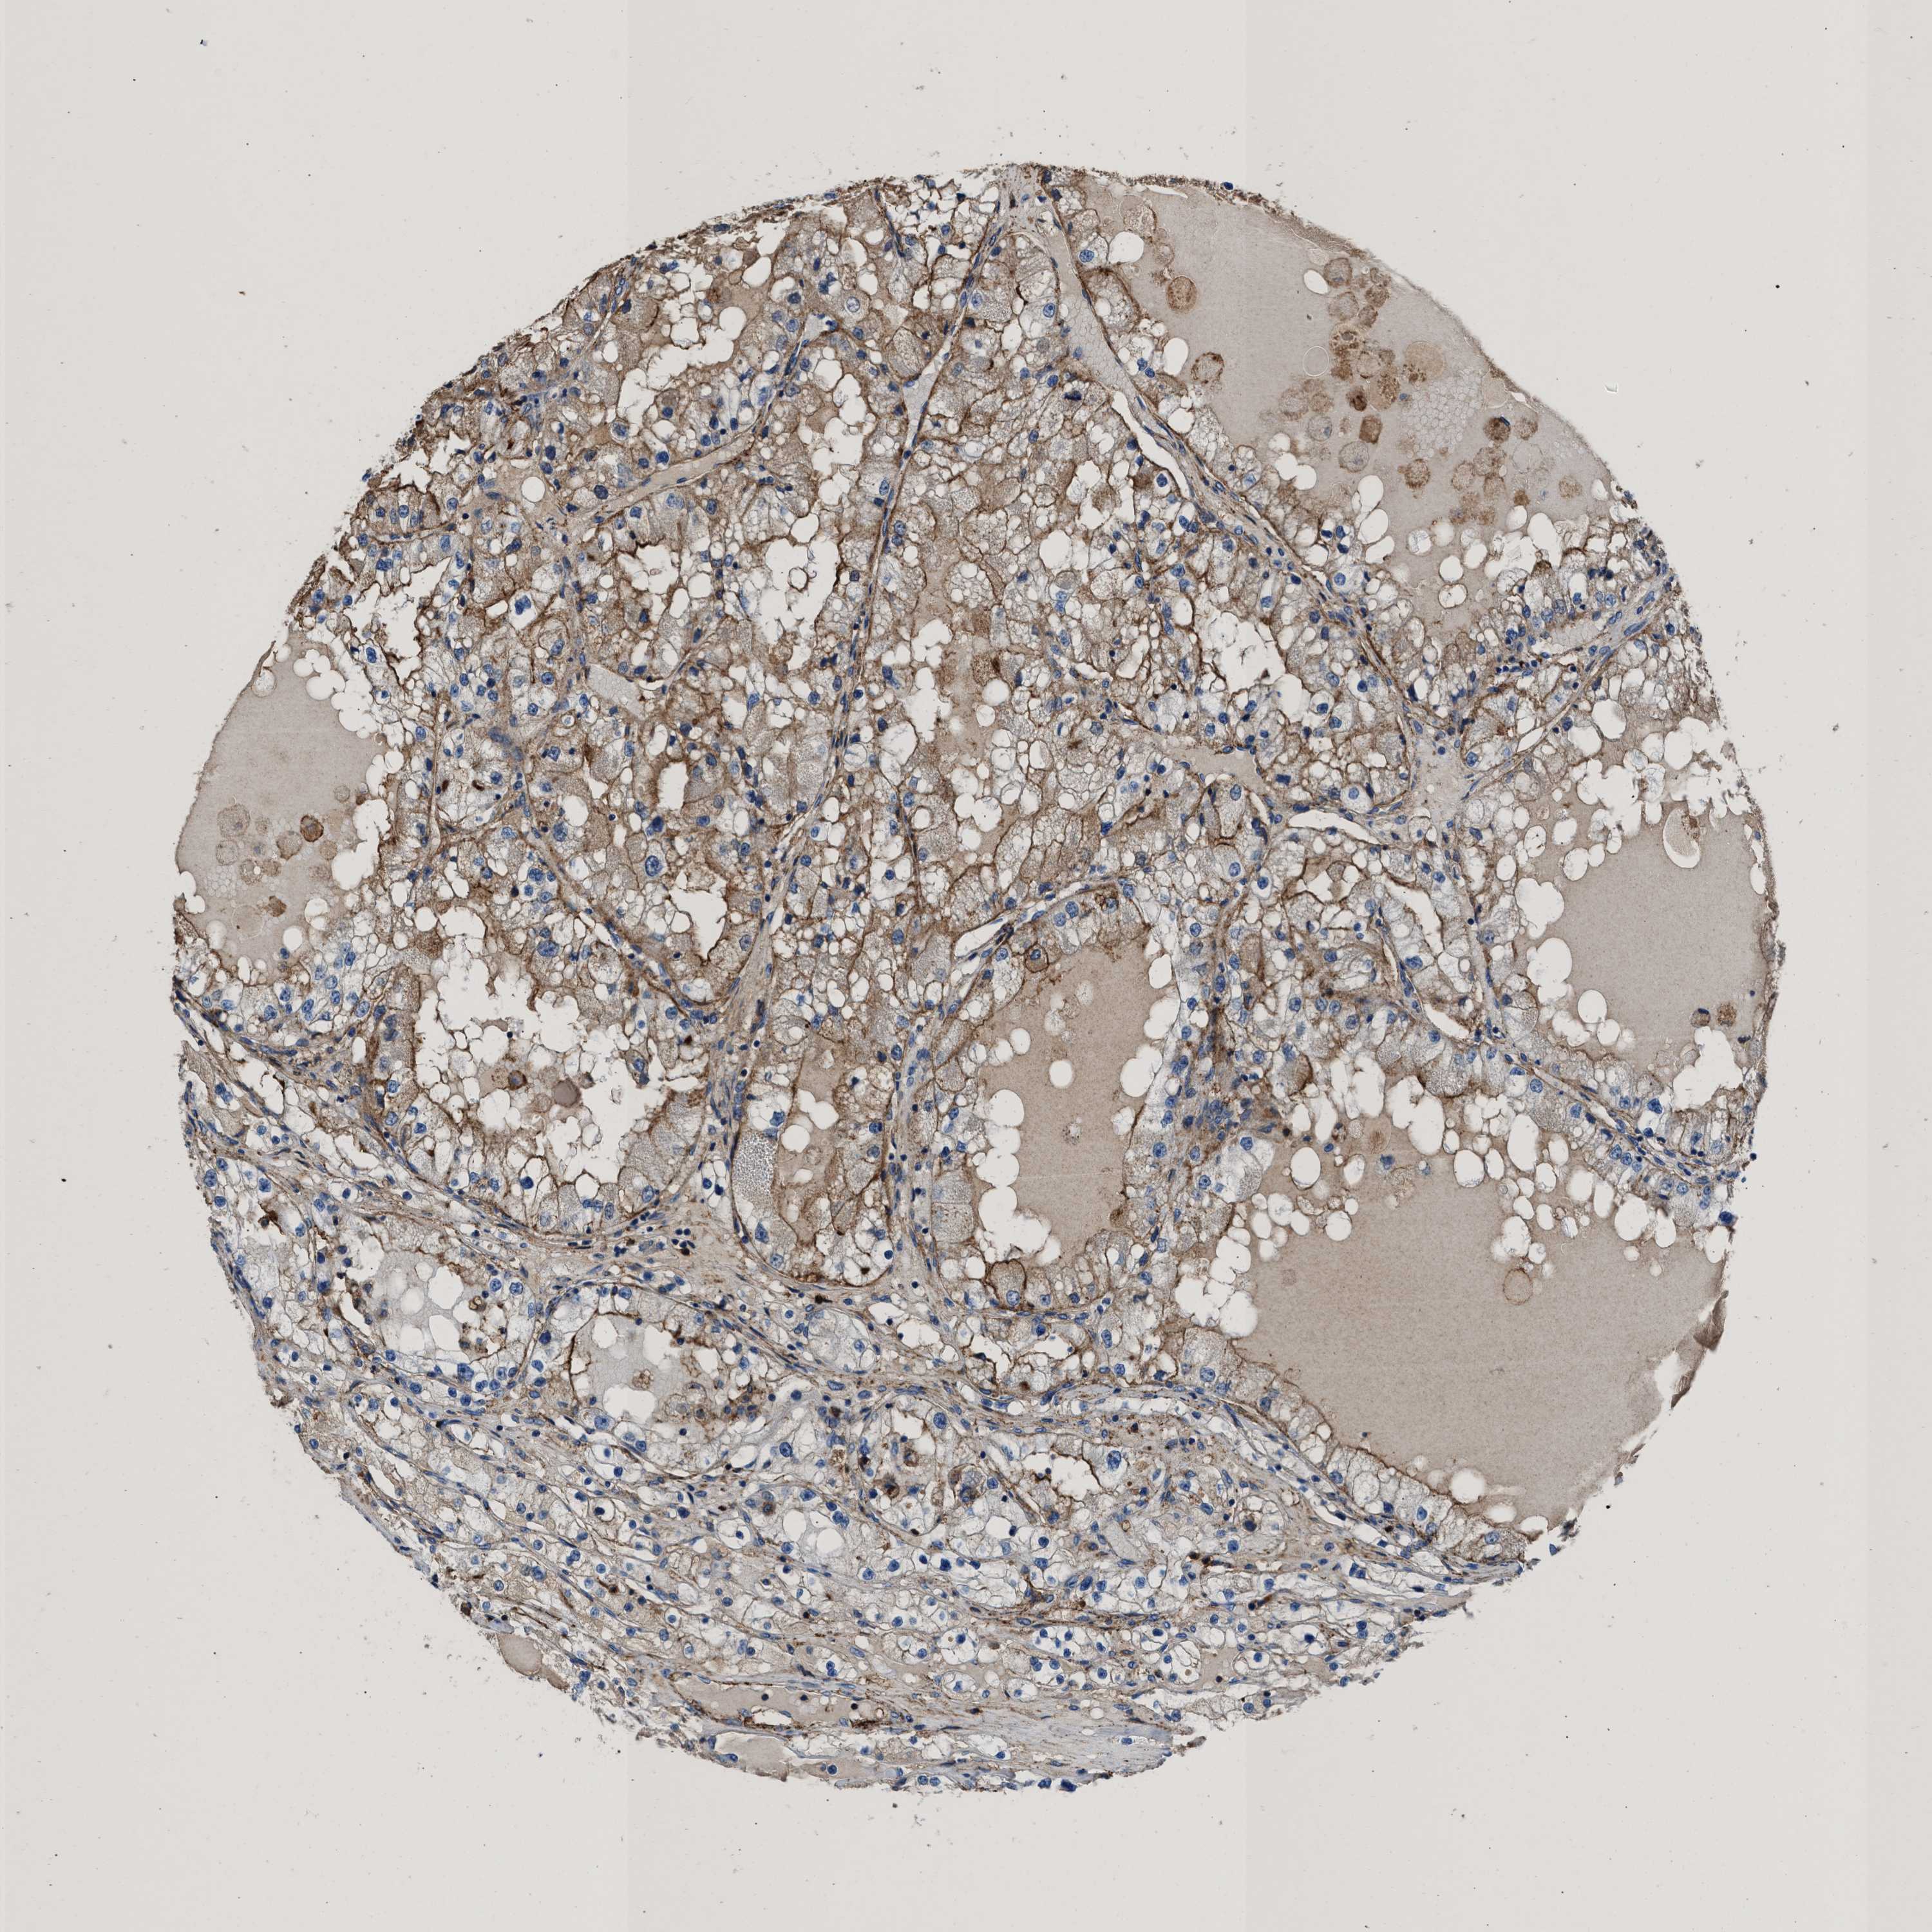

KIDNEY RENAL CLEAR CELL CARCINOMA (TCGA) - Interactive survival scatter ploti

The Survival Scatter plot shows the clinical status (i.e. dead or alive) for all individuals in the patient cohort, based on the same data that underlies the corresponding Kaplan-Meier plots. Patients that are alive at last time for follow-up are shown in blue and patients who have died during the study are shown in red.

The x-axis shows the expression levels (FPKM) of the investigated gene in the tumor tissue at the time of diagnosis. The y-axis shows the follow-up time after diagnosis (years). Both axes are complimented with kernel density curves demonstrating the data density over the axes. The top density plot shows the expression levels (FPKM) distribution among dead (red) and alive patients (blue). The right density plot shows the data density of the survived years of dead patients with high and low expression levels respectively, stratified using the cutoff indicated by the vertical dashed line through the Survival Scatter plot. This cutoff is automatically defined based on the FPKM cutoff that minimizes the p-score. The cutoff can be changed by dragging the vertical line or by entering a cutoff value in the square labeled "Current cut-off".

Under the Survival Scatter plot the p-score landscape (black curve; left axis) is shown together with dead median separation (red curve; right axis). Dead median separation is the difference in median mRNA expression between patients who have died with high and low expression, respectively. It is calculated as follows: median FPKM expression of dead patients with high expression - median FPKM expression of dead patients with low expression. This is intended to aid the user in visually exploring custom cutoffs and the associated p-scores and dead median separation.

Individual patient data is displayed and can be filtered by clicking on one or more of the category buttons on the top of the page. Categories describing expression level and patient information include: high, low, alive, dead, female, male and tumor stages. The scale of the x-axis can be toggled between linear and log-scale by clicking on the "x log" button. Mouse-over function shows TCGA ID, patient information and mRNA expression (FPKM) for each patient.

& Survival analysisi

Kaplan-Meier plots summarize results from analysis of correlation between mRNA expression level and patient survival. Patients were divided based on level of expression into one of the two groups "low" (under cut off) or "high" (over cut off). X-axis shows time for survival (years) and y-axis shows the probability of survival, where 1.0 corresponds to 100 percent.

KCNQ4 is not prognostic in Kidney Renal Clear Cell Carcinoma (TCGA)

TCGA RNA samplesi

RNA-seq data is reported as average FPKM (number Fragments Per Kilobase of exon per Million reads), generated by the The Cancer Genome Atlas (TCGA) .

Normal distribution across the dataset is visualized with box plots, shown as median and 25th and 75th percentiles. Points are displayed as outliers if they are above or below 1.5 times the interquartile range. FPKM values of the individual samples are presented next to the box plot.

Average pTPM 0.1

Number of samples 521